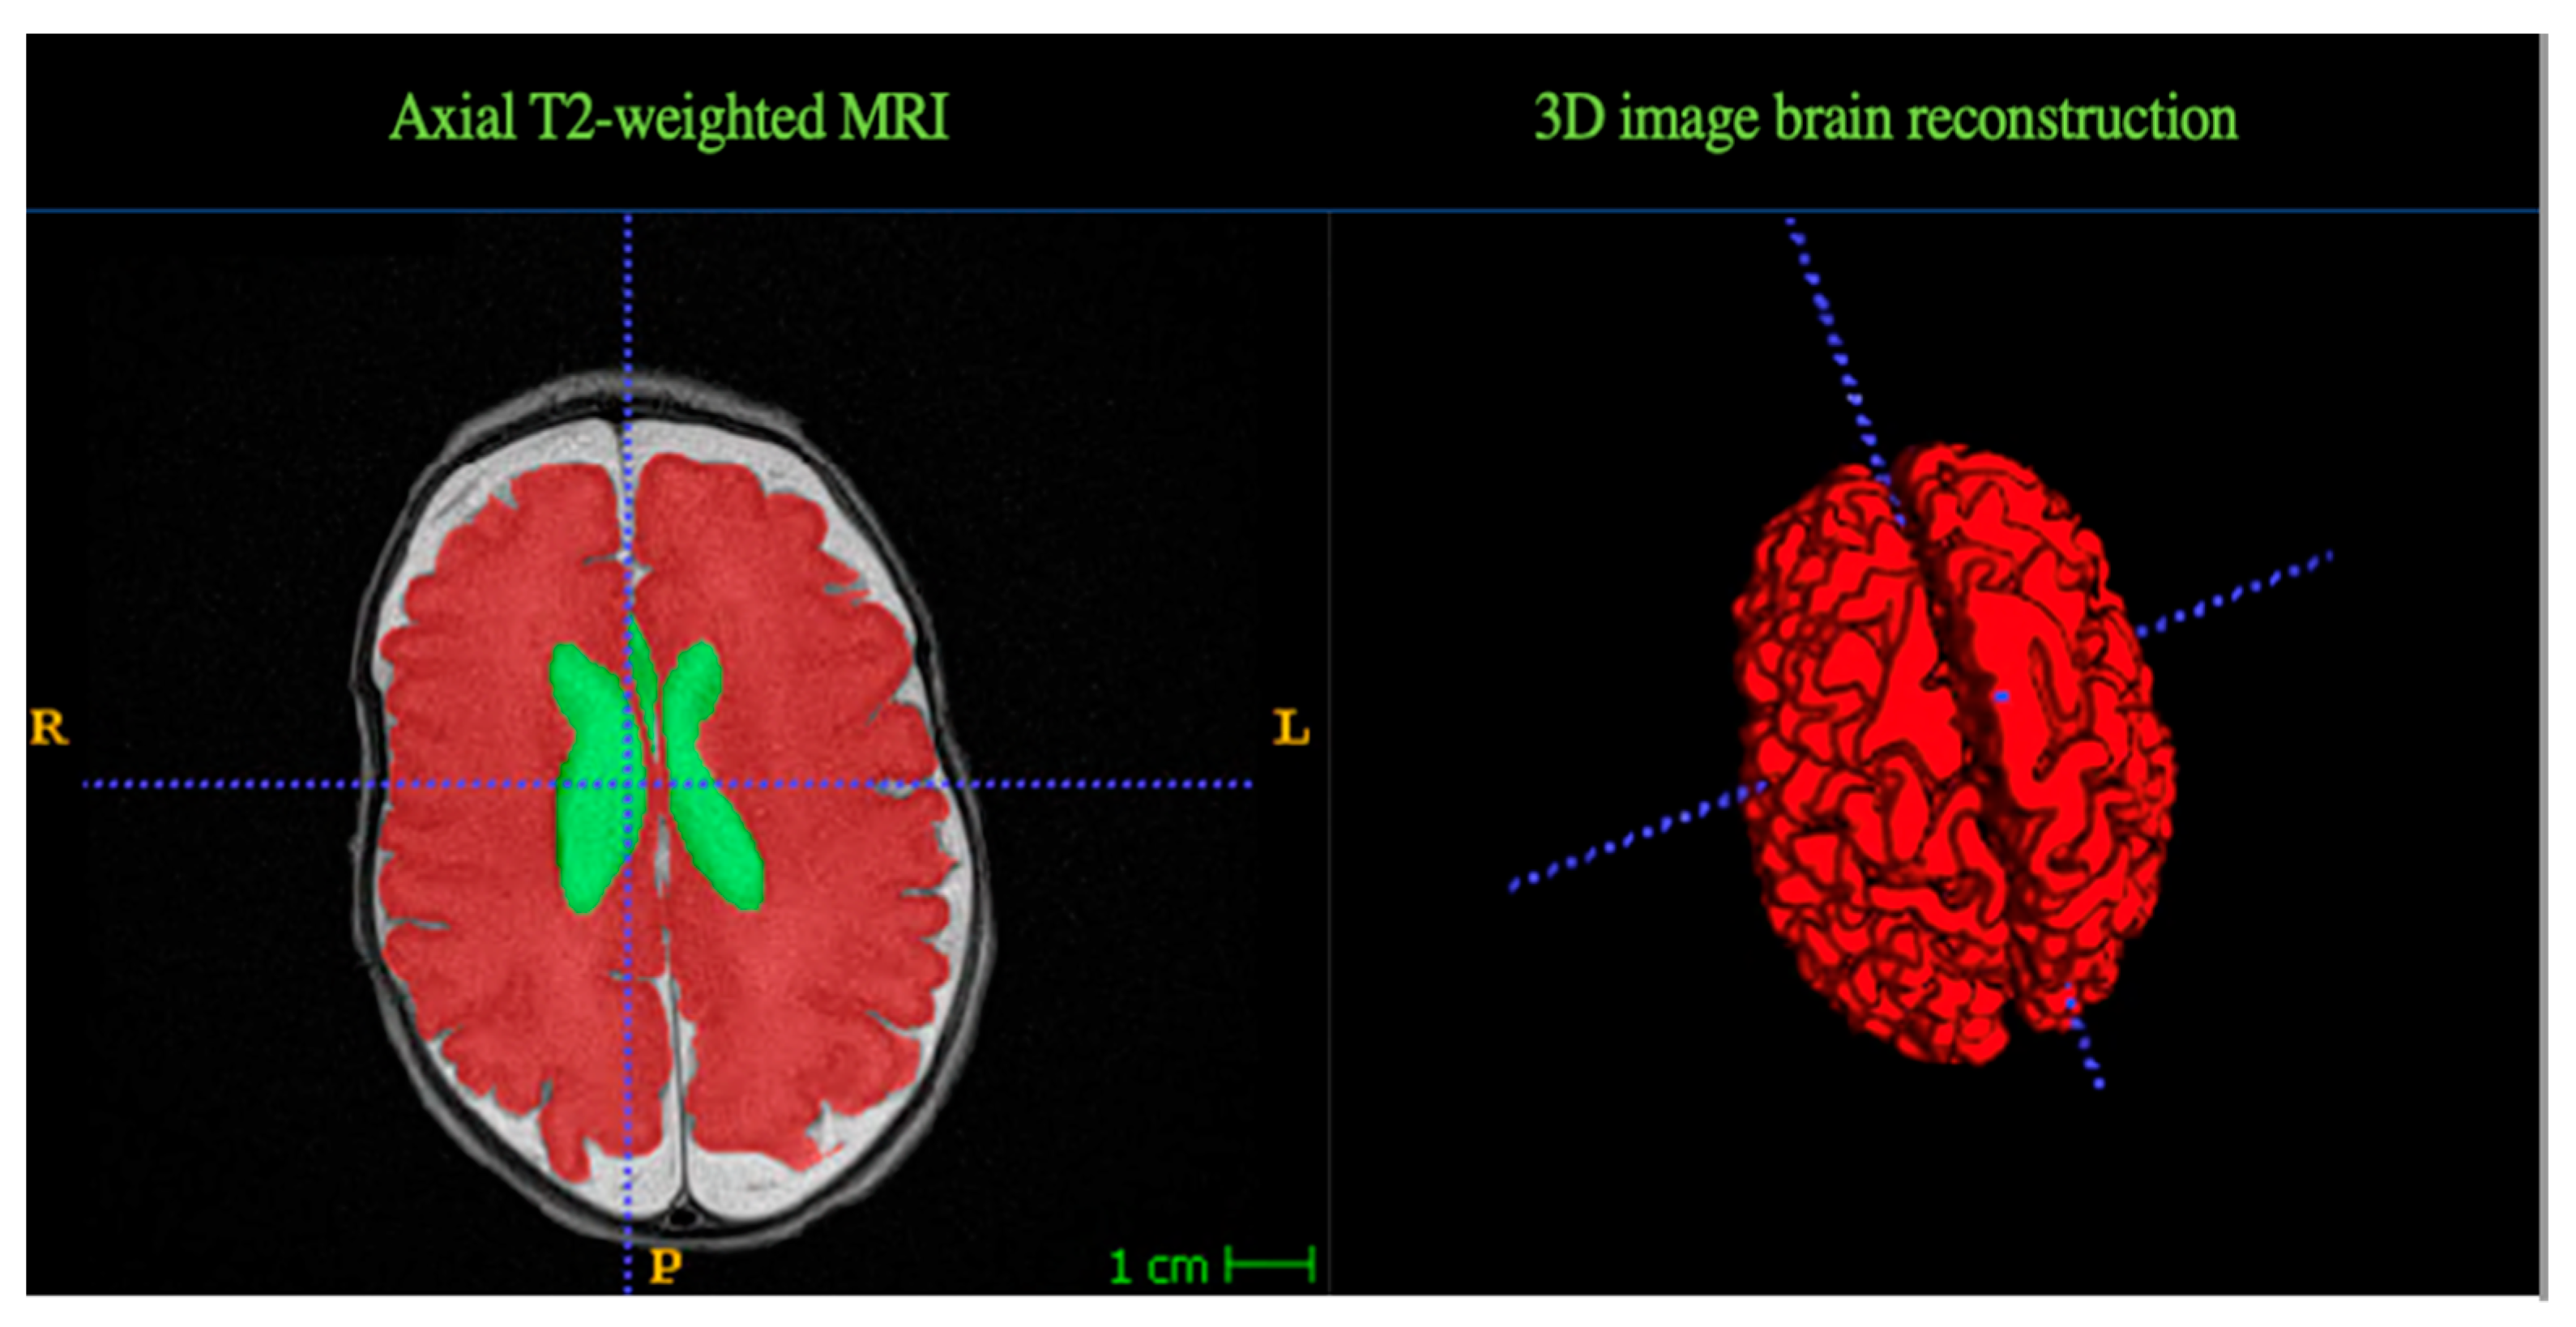

2.3. MRI Data Acquisition